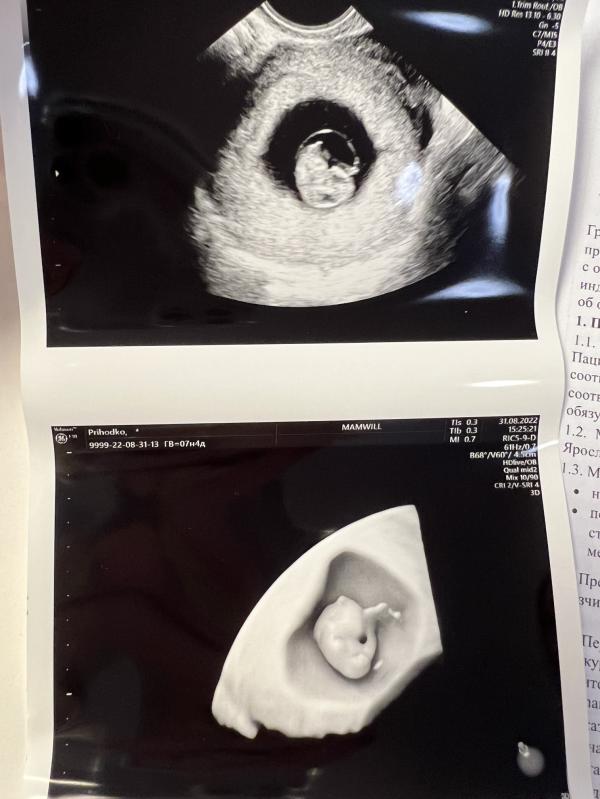

7 недель полёт нормальный 💫

Увидела свою кроху

Есть уже зачатки ручек и ножек🥰 развиваемся по сроку

А вроде же нельзя на маленьких сроках 3д узи 🙄

Врач с огромным стажем сделала

Думаю страшного в этом ничего нет

Какая красота 😍 тоже буду делать 3D узи, на память)))

Господи, потрясающие снимки 😍